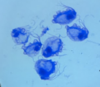

Leishmania sp.: Promastigotes

- Leishmania sp.*: Promastigotes

- Extracellular forms*